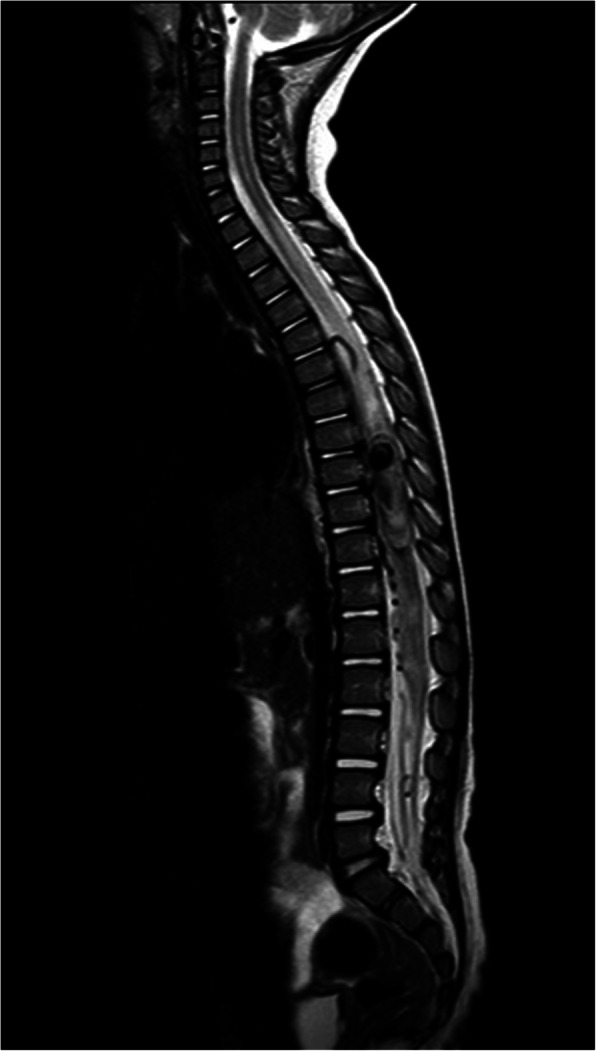

A 15-month-old 12.7 kg female presented with 1 week of fever, urinary retention, and subacute onset of paraplegia 1 day prior to admission. Her medical history was significant for birth at 36 weeks’ gestation and a 10-day hospitalization for treatment of congenital syphilis. Initial presentation was at another hospital where lumbar puncture showed leukocytosis, elevated protein, positive red blood cells, and no glucose. Blood and cerebral spinal fluid (CSF) cultures were negative, along with rapid CSF polymerase chain reaction. The patient was started on ceftriaxone, vancomycin, and acyclovir. MRI showed a lesion from T8-L1 (Fig. 1). The patient was transferred to our hospital for further management. She was able to move her upper but not her lower extremities at presentation to emergency room.

Fig. 1.

Sagittal T2 image of the spine demonstrates a mass with heterogeneity and flow voids from the level of T9 to T12 depicting the spinal AVM with pseudo aneurysm. Additionally, at the level of T6/T7 there is a flow void corresponding to the spinal artery of Adamkiewicz (anterior spinal artery) which demonstrates arteriomegaly